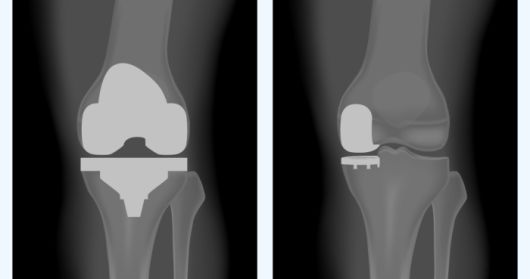

무릎 인공관절 치환술은 수술 범위에 따라서 크게 두 가지 종류가 있습니다. 무릎 관절이 많이 손상됐을 때 해당 부위를 모두 제거하고 인공관절로 바꾸는 '전치환술’과 손상된 일부분만 교체하는 '부분 치환술’입니다.

보통 손상된 무릎 관절을 모두 인공관절로 대체하는 전치환술의 치료 결과가 더 좋을 것으로 생각할 수 있습니다. 하지만 부분 치환술도 1990년대 이후 많이 발전해서 치료 성공률이 전치환술과 비슷해졌습니다.

특히 부분 치환술은 피부 절개 및 골 절제 부위가 작고, 통증이 적어서 환자의 수술 부담이 적습니다. 때문에 회복이 빠르고, 수술 후 관절 운동 범위 및 기능 회복에 더 유리합니다.

손동욱 교수는 "하지만 모든 환자에게 부분 치환술을 적용할 순 없다"며 "수술 전 자기공명영상(MRI) 등 정밀한 진단을 통해서 다리 변형이 심하지 않고, 관절 운동 범위가 90도 이상이며, 관절염이 특정 부분에만 국한돼 있다는 것이 충분히 확인돼야 한다"고 설명했습니다.